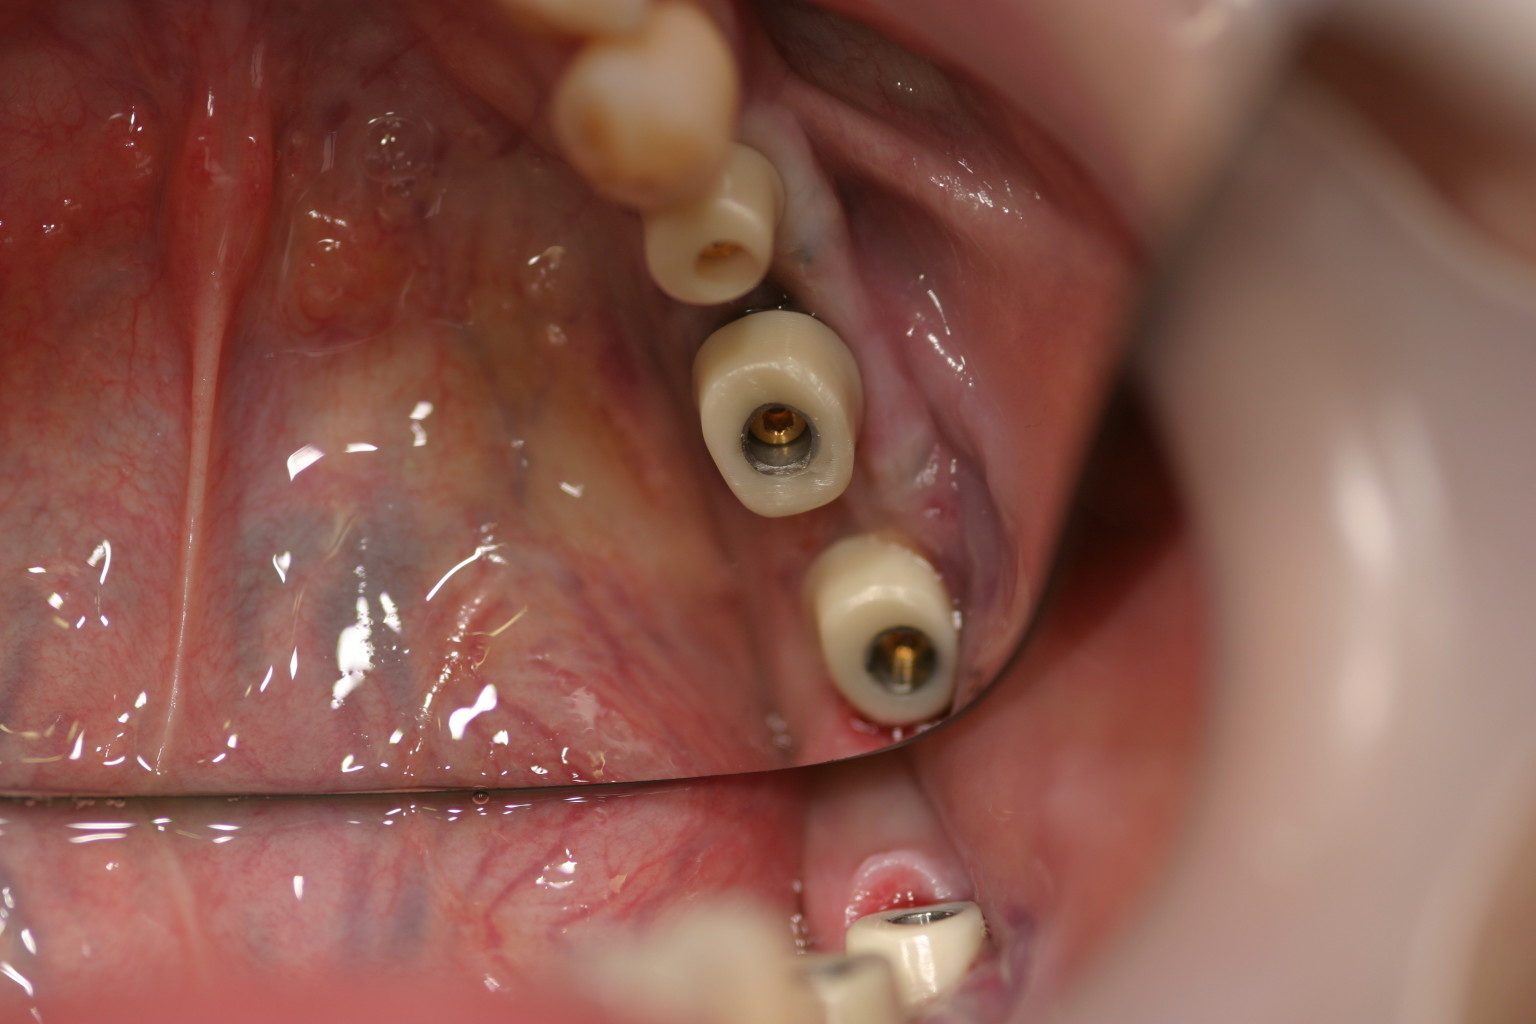

左下567番インプラントジルコニアアバットメント及びジルコニアセラミッククラウン装着